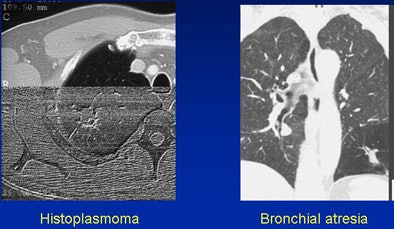

Conversely, there are many normal structures that mimic lung nodules, yielding potential false-negative calls, White said. These include granulomas, hamartomas, round pneumonia or atelectasis, arteriovenous malformation, and bronchial atresia.

|  |

| False-negative: Histoplasmoma (left) and air trapping in the setting of atresia (right). |